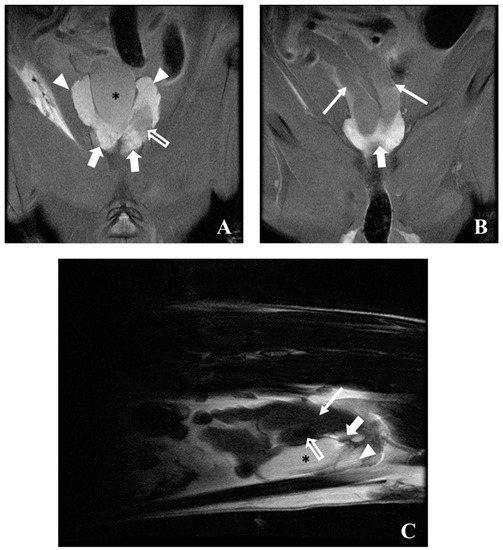

5.3. Magnetic Resonance Imaging (MRI)